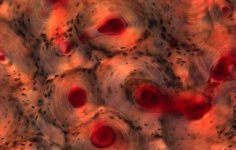

Levenhuk 850B – бинокулярный биологический микроскоп, с помощью которого можно вести наблюдения не только в светлом, но и в темном поле. Применяется в медучреждениях разного типа для урологических, дерматологических, биологических, биохимических, патологоанатомических, цитологических, гематологических и общеклинических лабораторных исследований.